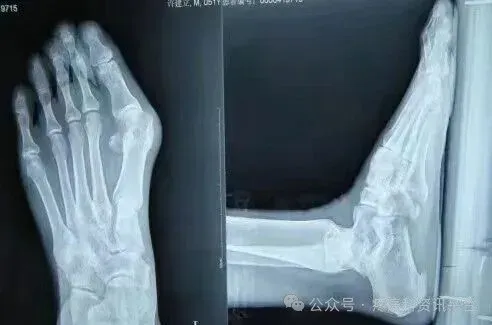

原石家庄市三院副院长冯建书亲自讲课示教,患者身边近距离看手术,可随时提问。冯建书:原石家庄第三医院(石家庄市骨科医院)副院长 手足外科主任可开发票,会后由承办单位石家庄君臣佐使会议服务有限公司提供会务费发票.图为术前术后对比图

本次培训以“理论+临床观摩+学员亲自动手截骨(动物标本)"为主,三位一体全面掌握这项技术。在上午理论授课环节,冯主任亲授临床经验和技巧,共同分享多年临床经验和研究心得,让大家在学习中相互交流,在实践中共同进步。培训间隙,老师会教大家术后包扎要领、手术松解等内容下午安排进手术室观摩,老师边手术边讲解在术中需要注意的地方,通过近距离的观摩深入掌握了解这项技术